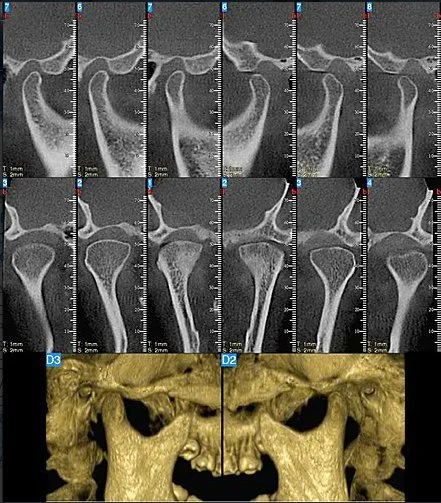

Tomografía de ATM

La tomografía de la articulación temporomandibular es un estudio tridimensional que permite evaluar con alta precisión las estructuras óseas de la ATM, incluyendo cóndilos y fosa glenoidea, facilitando la detección de alteraciones estructurales, asimetrías y cambios degenerativos, aportando información clave para el diagnóstico y la planificación de tratamientos en especialidades como ortodoncia, cirugía oral y maxilofacial.